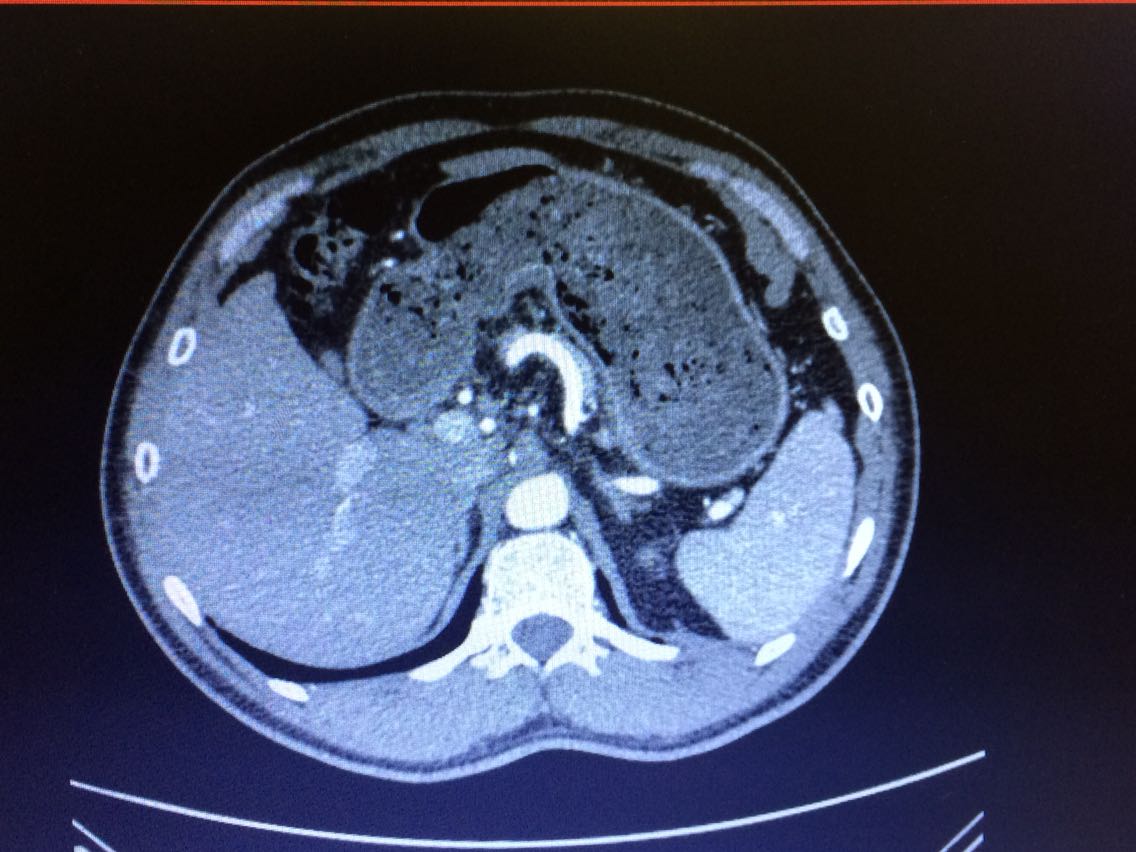

查体:全身皮肤未见紫纹、痤疮,无多毛,无“水牛背”、“满月脸”。 心肺腹阴性。  辅查:2015年外院“醛固酮” 800+(具体不详)。 2016年10月冠脉CTA:1.左冠状动脉前降支近中段血管壁见多处偏心性混合密度斑块,伴近段局部管腔轻度狭窄,中段管腔局限性中度狭窄。2.回旋支近段血管壁见偏心性钙化斑,伴局部管腔轻度狭窄;中段血管壁见非钙化斑块,局限性管腔呈中-重度狭窄。3.右侧冠状动脉近段血管壁见偏心性钙化及非钙化斑块,管腔轻度狭窄。后降支局部管腔明显狭窄。前降支中段肌桥(纵深型)。5.主动脉硬化。 入院查:肝功:谷丙转氨酶:ALT 63U/L,谷草转氨酶:AST 46U/L。 电解质:钾:K 3.06mmol/L,二氧化碳结合力:CO2 33.3mmol/L。  肾功、血常规未见明显异常。 立位高血压四项(初筛):醛固酮(ALD):680.54,ARR:138.89,血管紧张素I(37℃):0.88,血管紧张素I(4℃):0.39。 皮质醇(0:00):55.90 nmol/L,皮质醇(08:00):293.50 nmol/L,皮质醇(16:00):140.50 nmol/L。促肾上腺皮质激素(00:00):1.23 pmol/L,促肾上腺皮质激素(08:00):4.70 pmol/L,促肾上腺皮质激素(16:00):3.25 pmol/L。17-羟皮质类固醇(17-OHCS):9.96 mg/24h尿,17-酮皮质类固醇(17-KS):15.92 mg/24h尿。尿香草扁桃酸(VMA):5.42 mg/24h尿,尿液醛固酮(ALD):25.58↑ ug/day。卡托普利试验:立位高血压四项(服药前)固酮(ALD):664.33↑ pmol/L。ARR:265.73↑;立位高血压四项服药后(2小时):醛固酮(ALD):534.47↑ pmol/L,ARR:184.30↑。胸部正侧位: 左侧膈面改变不除外膈下病变,建议CT检查。肾上腺CT平扫+增强:1、左侧肾上腺外侧支结节,考虑腺瘤。 2、左肾小结石。(左侧肾上腺外侧支局部增粗,见小结节状密度影,大小约1.5cm×1.2cm,病灶内可见少许脂肪密度影,增强后轻度强化) 。双侧颈动脉(含颈总、颈内、颈外)彩超:右侧颈动脉内中膜增厚。 肝、胆、胰、脾B超、肾动脉、肾内小动脉(双侧)彩超未见明显

病例特点:高血压6年,血压最高达247/155mmHg;无高血压家族史,使用多种降压药血压仍控制不理想;低血钾,经积极补钾血钾仍偏低;高血压病程6年即已出现冠脉多发斑块、狭窄。诊断:1.原发性醛固酮过多症 2.冠状动脉粥样硬化性心脏病 3.肝功能异常 4.低钾血症 5.肾结石 出院带药:螺内酯片 40mg 每日三次、 阿托伐他汀钙分散片 20mg 每日一次、氯化钾缓释片 1g 每日三次 、特拉唑嗪片 4mg 每日两次(早,晚) 。建议及早行手术治疗。